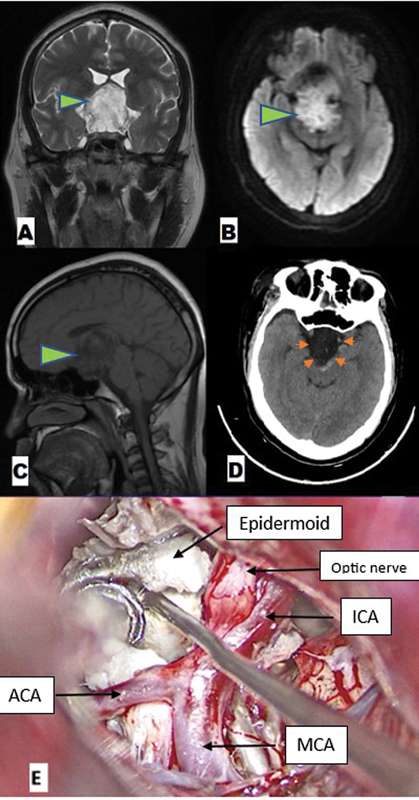

Background  In recent times, the supraorbital approach via eyebrow incision has gained tremendous popularity in targeting the anterior skull base and few middle cranial fossa lesions, over the more traditional pterional and frontotemporal approaches. However, the extremely narrow viewing angle through this approach requires frequent adjustments of the operating table and microscope for optimal visualization. Illumination via such a small opening in such deep-seated location was another limiting factor. Keeping these problems and cumbersomeness of microscope in mind, experienced surgeons gradually shifted over to purely endoscopic or endoscope-assisted supraorbital keyhole approaches. But it was also limited due to high cost, steep learning curve, and difficulties faced in blood-filled cavities. To circumvent these limitations of the microscope and endoscope, the supraorbital keyhole approach can be accomplished with an exoscope (ExSOKHA). Although various cranial procedures using exoscope have become well established in contemporary times, there is paucity of studies and literature dedicated specifically to this minimally invasive supraorbital keyhole approach using the exoscope only. Here, we aim to study the feasibility and usefulness of the exoscope in targeting skull base lesions via the supraorbital keyhole approach to determine if it can be used in learning while transitioning from the microscope to the endoscope, with the primary objective being the user friendliness of the exoscope in the SOKHA technique. Materials and Methods  This prospective observational study was conducted in the department of neurosurgery over a period of 7 years. The sample size was 50. The study utilized an exoscope and support arm-2D VITOM rigid-lens telescope (Model 28095 VA, Karl Storz Endoscopy, Tuttlingen, Germany) with a 10-mm outer diameter and a shaft length of 14 cm, light source (Xenon Nova 300, Karl Storz GmBH and Co., Tuttlingen, Germany), camera head, video display monitor, and a holding arm. Results  Out of 50 cases, the majority were pituitary adenomas (30%) and meningiomas (38%), with aneurysms comprising 6%; only 4 cases (8%) had inadvertent frontal sinus opening and 2 cases (4%) had postoperative cerebrospinal fluid (CSF) leak. The duration of surgery ranged from 2 to 4 hours, with the shortest being for aneurysm clipping/CSF rhinorrhea and the longest for meningioma and pituitary adenoma excision. Intraoperatively, exoscope repositioning for adjustment was required for a maximum of nine times, which significantly reduced the overall operative time. Eight cases had near total excision; the remaining tumors had complete excision and the aneurysms had complete clipping. Hospital stay ranged from 4 to 7 days, with mean intensive care unit (ICU) stay of 3 days. None of the patients had any surgical cosmetic deformity. The Glasgow Outcome Scale of all patients was good (4/5 or 5/5). Thus, ExSOKHA offered good results in terms of operative time, frequency of adjustments, completeness of excision and clipping, and recurrence. The results were also comparable for other parameters like inadvertent frontal sinus violation, postoperative CSF leak, hospital stay, cosmetic deformity, and outcome. Conclusion  The exoscope is a further advancement in the telescopic system, which provides a higher focal length (250-550 mm), ergonomically superior surgery with better depth illumination in skull base lesions approached via the supraorbital keyhole approach, significantly reducing operative time and improving resection margins due to increased corner visibility and easy maneuverability. It helps learn neuroendoscopy with the familiar principles of microneurosurgery, possibly shortening the learning curves. It bridges the gap between the endoscope and the microscope as the surgery is performed while viewing the screen (as in endoscope), but without needing to take the scope inside the operative field (as in microscope), making it easier to maneuver while also limiting space occupancy.